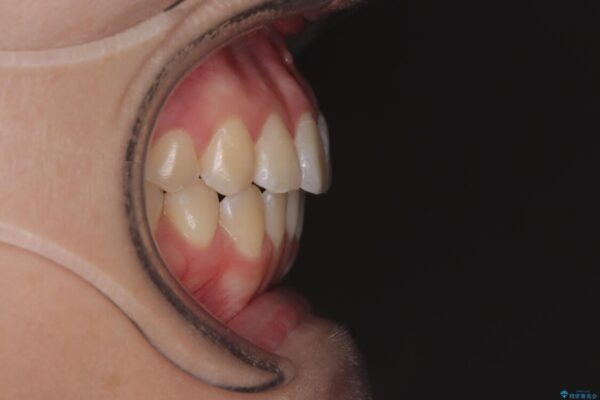

治療途中

• 前歯のねじれ・ガタガタを10か月で改善!20代女性の矯正治療|クリアブラケットでむし歯になりにくい歯並びへ改善 治療途中画像

診察の結果、上下の前歯部に**叢生(そうせい/歯のガタガタ・重なり)**が認められました。

特に上の前歯にはねじれや重なりがあり、審美的にも清掃性にも影響している状態でした。